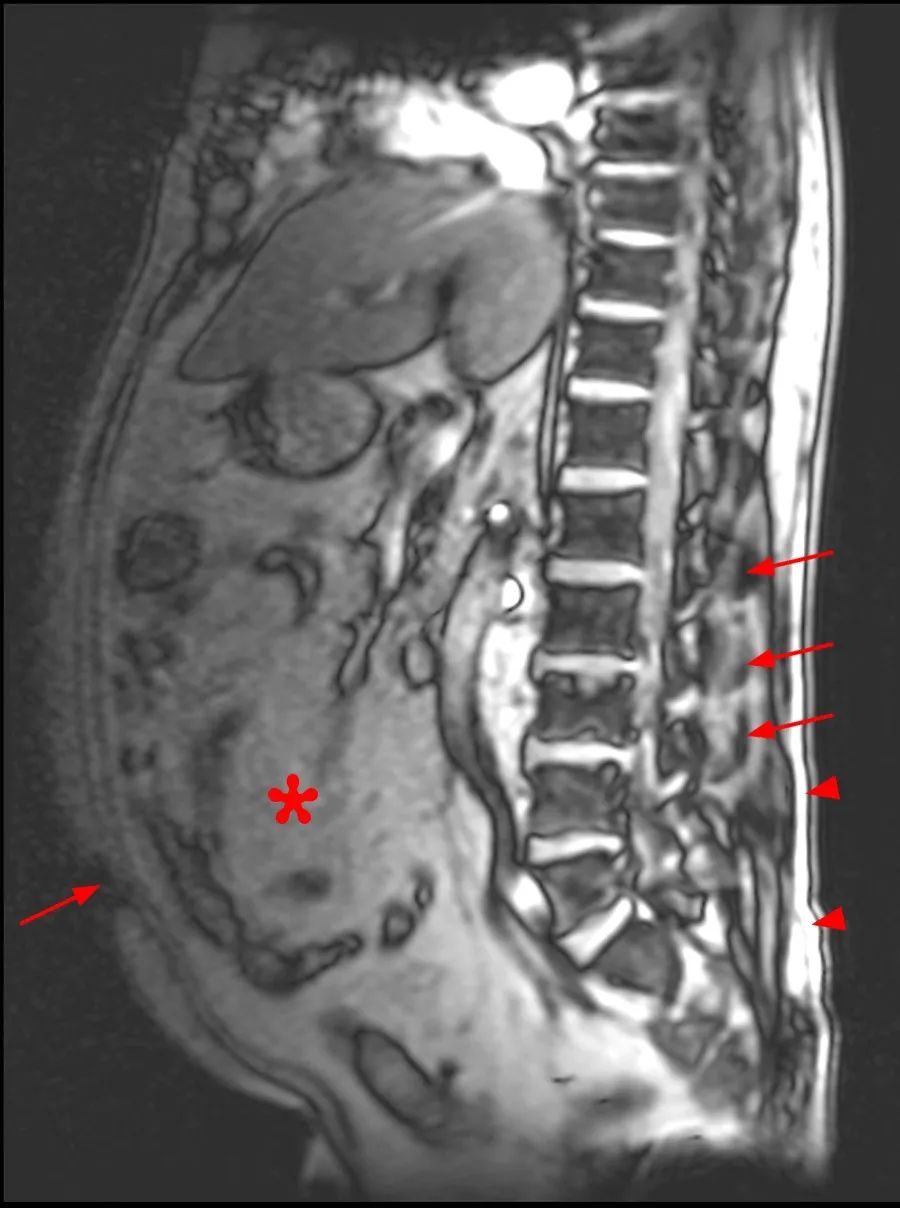

男,45 岁,1 年前出现慢性腰痛、双侧大腿麻木和无力感。临床查体无神经功能缺损。

本次腰椎 MR 检查:你发现了什么?

4.5 年前和现在的腰椎 MR T2WI 轴位对比:L4-L5 水平,现在的 MR 发现马尾神经位置前移,更加聚拢;而 4.5 年前的 MR 发现马尾神经位置靠后,分散。

回过头再看第一个病例,发现椎管内硬膜外脂肪增多,向前推挤马尾神经,使其相对聚拢

同样的,回头看第一个病例也会发现硬脊膜椎韧带,是由于硬膜外脂肪增多而把他显示出来